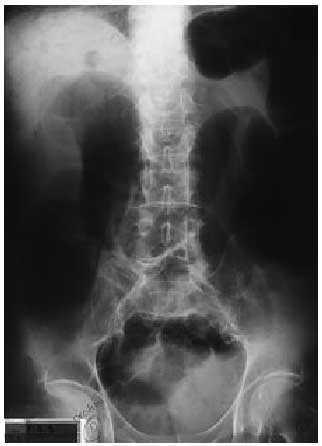

Radiografía simple de abdomen en decúbito supino (fig. 1): dilatación de asas de intestino, más llamativa en el colon, imágenes radiolucentes en la pared del colon ascendente (neumatosis), así como múltiples imágenes lineales radiolucentes con bordes bien definidos y proyectadas sobre silueta hepática.

Fig. 1.